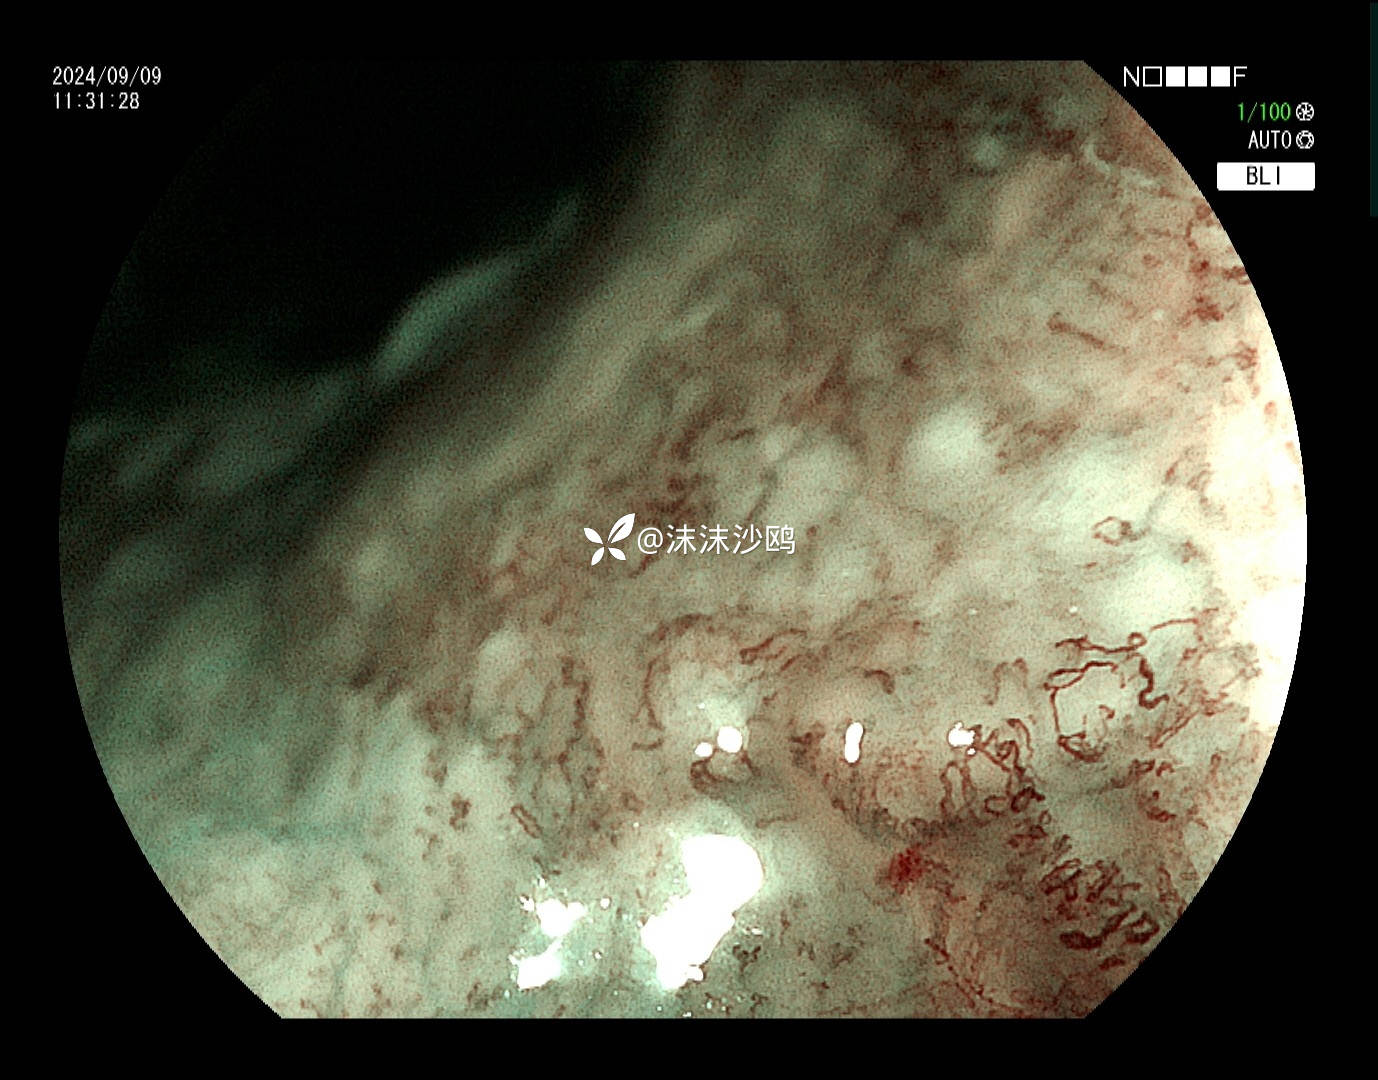

ME

非常适合碘染的病例,可惜没有卢戈氏碘,只能电子染色放大。病灶活检2块,因出血较多,没有再继续活检。

该患者平素无明显症状,吸气注气观察病灶延展性,柔软度可,白光观察粘膜呈现发红粗糙,BLI放大观察呈现明显茶褐色,可见B1型血管,局灶可见紊乱生长的B2型血管,并见AVA区域,感觉小于0.5mm。镜下考虑浸润深度,不超过SM1,应该有内镜下D的可能性。等病理结果,希望符合内镜诊断。